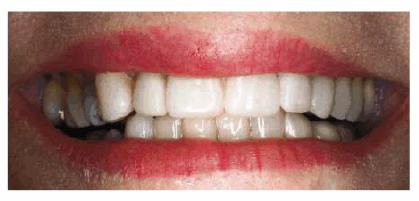

Figures 29-12A to C show a 75-year-old woman who presented

with severe root caries and moderate periodontal disease. Her daughter, who

disclosed that her mother was difficult to please, referred her. The daughter

was very supportive of her mother receiving dental treatment; however, her

mother was initially not interested. The mother did not think that the esthetic

aspect of dentistry was important. During consultation with the dentist, the

mother was informed of the infection in her mouth and the potential effect that

this could have on her future health and functionality. The patient consented

to have the maxillary arch restored with fixed prosthodontics. She refused to

accept treatment for her mandibular teeth, preferring to use her existing

partial denture. Figures 29-12D, and 29-12E show the final result after periodontal and

prosthodontic treatment. Although the patient was not particularly grateful to

have the dental treatment, her family was thrilled to have the caries infection

removed and the esthetic appearance improved. The patient lived with her

esthetically improved appearance for an additional 13 years.

Figure 29-12A to C: This 75-year-old woman had severe root caries and moderate periodontal disease.

Figure 29-12D: Although this woman stated that she would "just as soon have her teeth extracted," she was motivated to have both periodontal and prosthodontic treatment.

Figure 29-12E: The patient's smile after esthetic dental treatment shows just how much she appreciated her dental treatment.